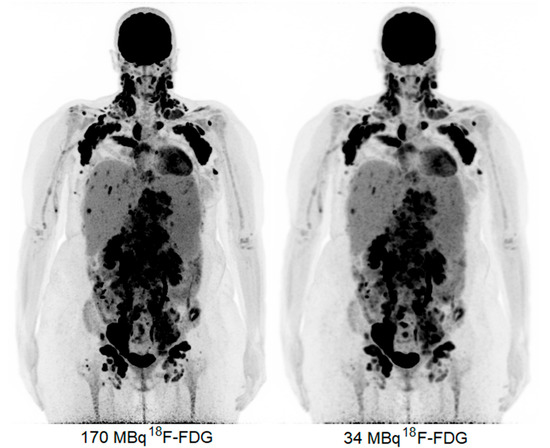

2. Case Presentation